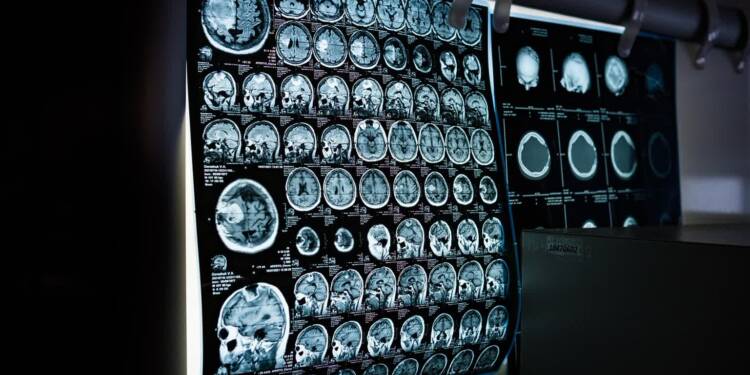

Naukowcy z Lublina będą opracowywać nową metodę diagnostyki i rehabilitacji dla pacjentów z chorobami neurologicznymi. Specjaliści z Politechniki Lubelskiej oraz Uniwersytetu Medycznego w Lublinie zbadają mózgowe korelacje w zakłóceniach postrzegania własnego ciała.

– Głównie będą badać pacjentów ze stwardnieniem rozsianym, a także po udarach niedokrwiennych – mówi kierownik Zakładu Neuropsychiatrii Klinicznej Uniwersytetu Medycznego w Lublinie dr hab. n. med. Paweł Krukow. – Długoterminowy cel całego projektu to jest właśnie dokładne określenie mechanizmów mózgowych zmian w percepcji ciała, które dla pacjentów mogą być naprawdę dość dramatycznym doświadczeniem. Te zakłócenia percepcji ciała są bardzo barwne. To są np. wrażenia, że moja kończyna jest obcą kończyną, że nie mam połowy ciała. Są to doświadczenia rzeczywiście bardzo dojmujące i też wcale nie do końca dobrze poznane.